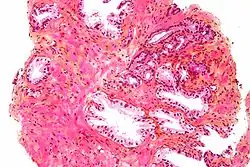

Microscopic glands of the prostate -

Microanatomy of a prostatic gland, showing both luminal cells and surrounding basal cells. H&E stain. -

The prostate consists of glandular and connective tissue.[2] Tall column-shaped cells form the lining (the epithelium) of the glands.[2] These form one layer or may be pseudostratified.[4] The epithelium is highly variable and areas of low cuboidal or flat cells can also be present, with transitional epithelium in the outer regions of the longer ducts.[10] Basal cells surround the luminal epithelial cells in benign glands. The glands are formed as many follicles, which drain into canals and subsequently 12–20 main ducts, These in turn drain into the urethra as it passes through the prostate.[4] There are also a small amount of flat cells, which sit next to the basement membranes of glands, and act as stem cells.[2]

The connective tissue of the prostate is made up of fibrous tissue and smooth muscle.[2] The fibrous tissue separates the gland into lobules.[2] It also sits between the glands and is composed of randomly orientated smooth-muscle bundles that are continuous with the bladder.[11]

Over time, thickened secretions called corpora amylacea accumulate in the gland.[2]